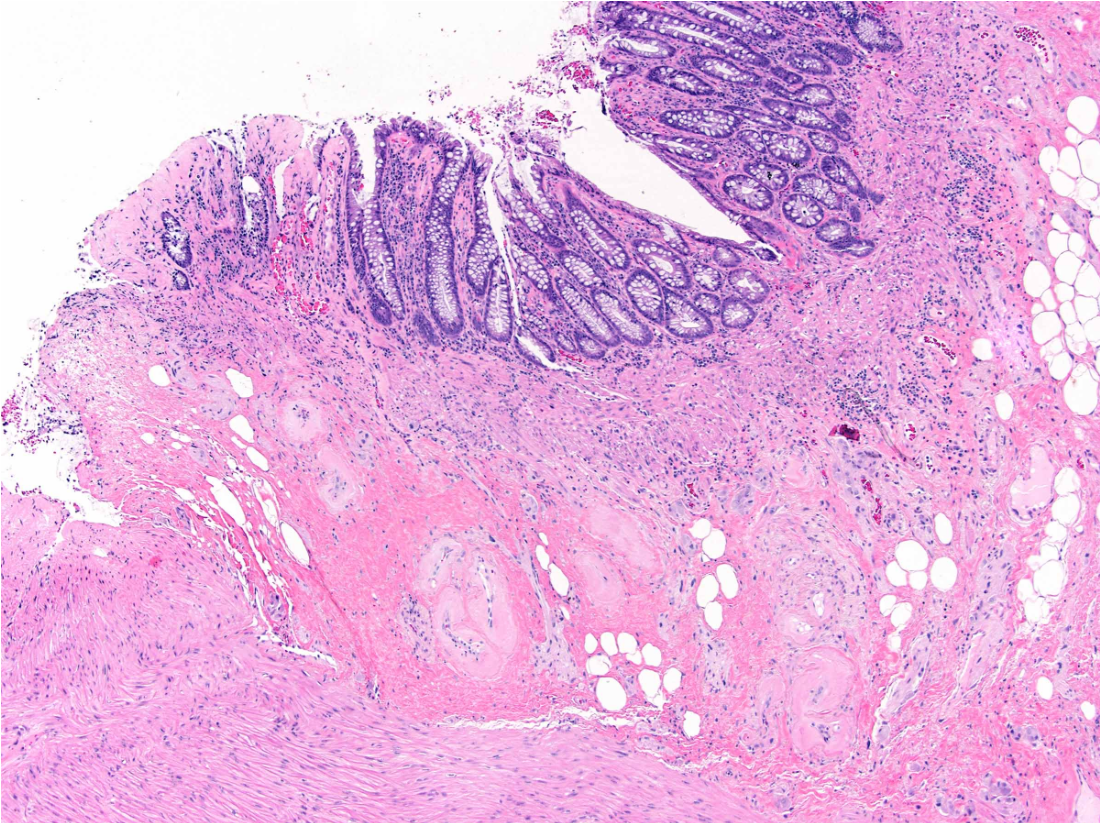

liver lesion bx

40F

translocation

A

HCC, fibrolamellar variant

Rare in peeps over 50 yrs

b/g liver non-cirrhotic

translocation: DNAJB1-PRKACA fusion gene

Trabecula, sheets or cords of neoplastic cells with abundant oncocytic cytoplasm cells in background of dense collagen bundles frequently arranged in parallel lamellae